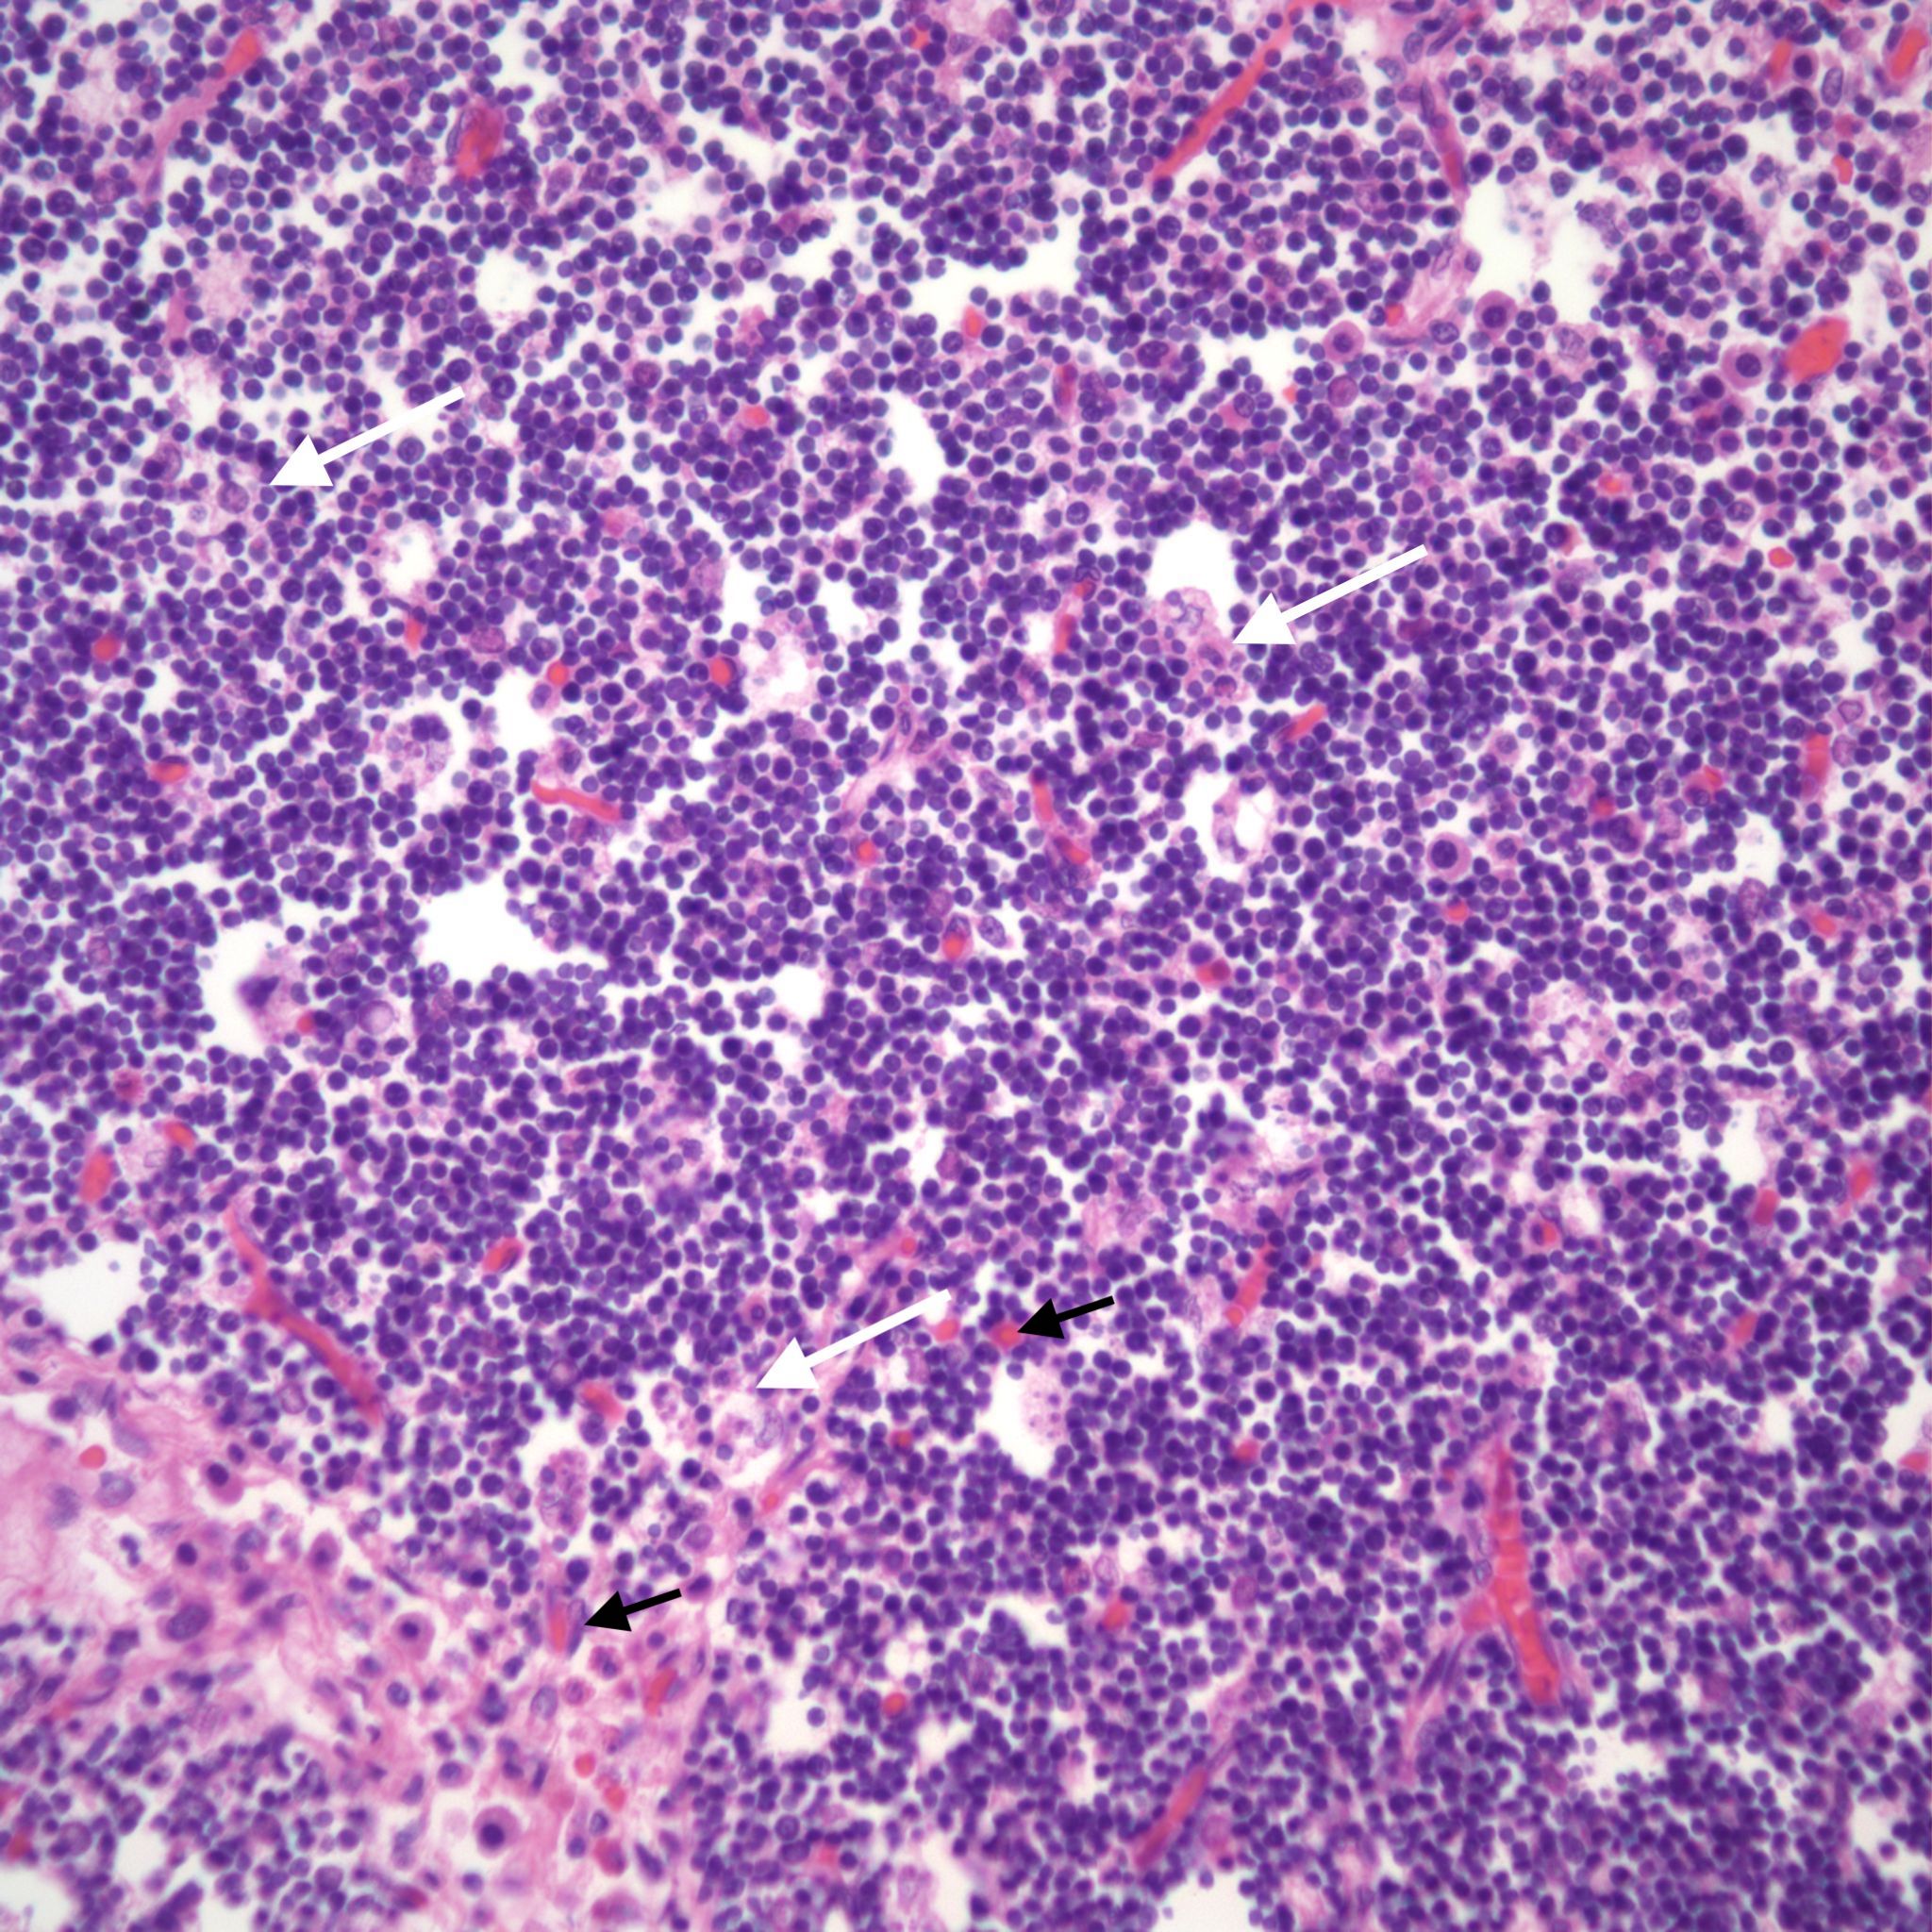

Petechial hemorrhages are usually scattered within the parenchyma, not just on the surface. (Fig 7,8)

They may be difficult to perceive in autolyzed tissue. Thymic petechiae have been associated with acute asphyxia in stillborn infants, such as with premature separation of the placenta[5, 6]. In this scenario, the petechiae are usually sparse, superficial, and as is also the case with thymic petechiae in SIDS, not on the cervical thymus. Larger, confluent hemorrhages in the thymus, often suggest a more systemic coagulation disorder. Thymic petechiae associated with asphyxia are often accompanied with other intrathoracic petechiae including on the visceral pleura and the epicardium. To interpret the meaning of these petechiae requires understanding the mechanism of petechial hemorrhage formation and then to relate that to the events that occur with acute intrauterine asphyxia.

The thymus normally involutes as the infant ages. However, in some stillborn infants, usually with a chronic stress such as infection, fetal hydrops or growth restriction, there is accelerated involution, that is loss of the lymphocytes in the cortex of the thymus. An early phase of this process is often seen in response to chorioamnionitis. In the acute cases, the prominent abnormality is a “starry sky” appearance due to the lymphorrhagia (phagocytosis) of cortical lymphocytes. Low magnification microscopy demonstrates open spaces in the cortex reminding some observers of a “starry sky”. (Fig 9,10) At higher magnification, these apparent spaces can be seen to be the cytoplasm of a large cell often with small, fading nuclei of small lymphocytes within.